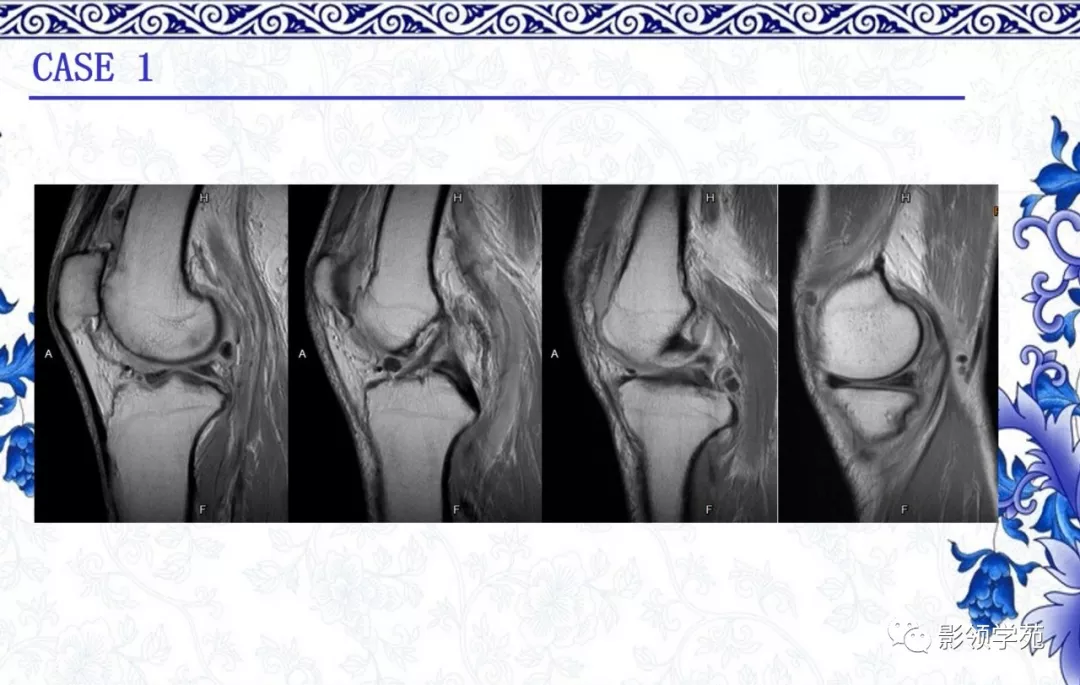

骨软骨瘤

· 良性肿瘤

·多见于30岁以下

·起源于软骨内化骨的骨骼,长骨干骺端多见

·影像表现:

1. 骨表面突起,背向关节,皮质及髓腔与母骨延续

2.软骨帽非矿化部分在磁共振T2WI呈高信号

3.成人软骨帽厚度超过1.5-2cm需怀疑恶变